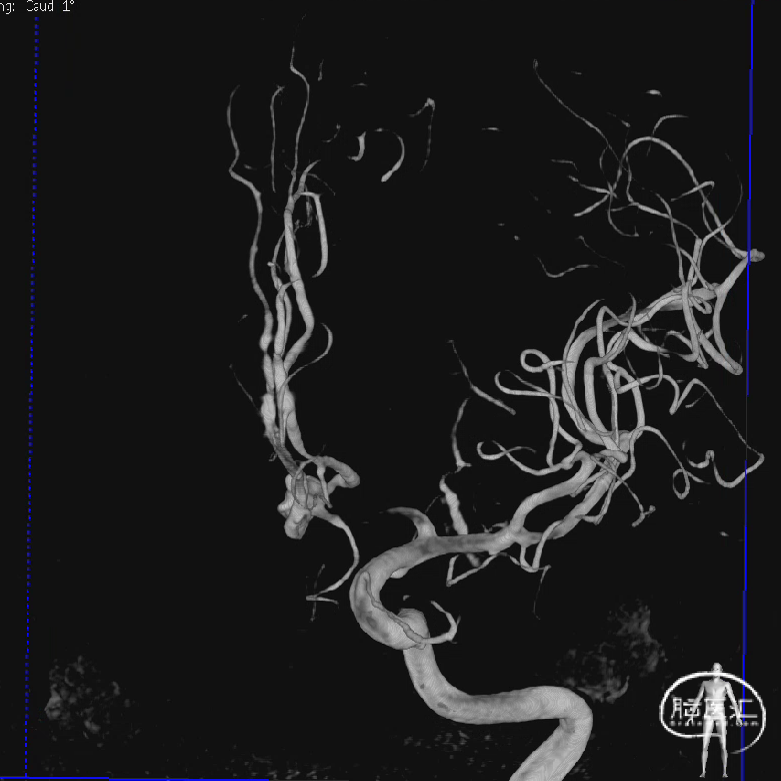

术前影像

术前DSA影像